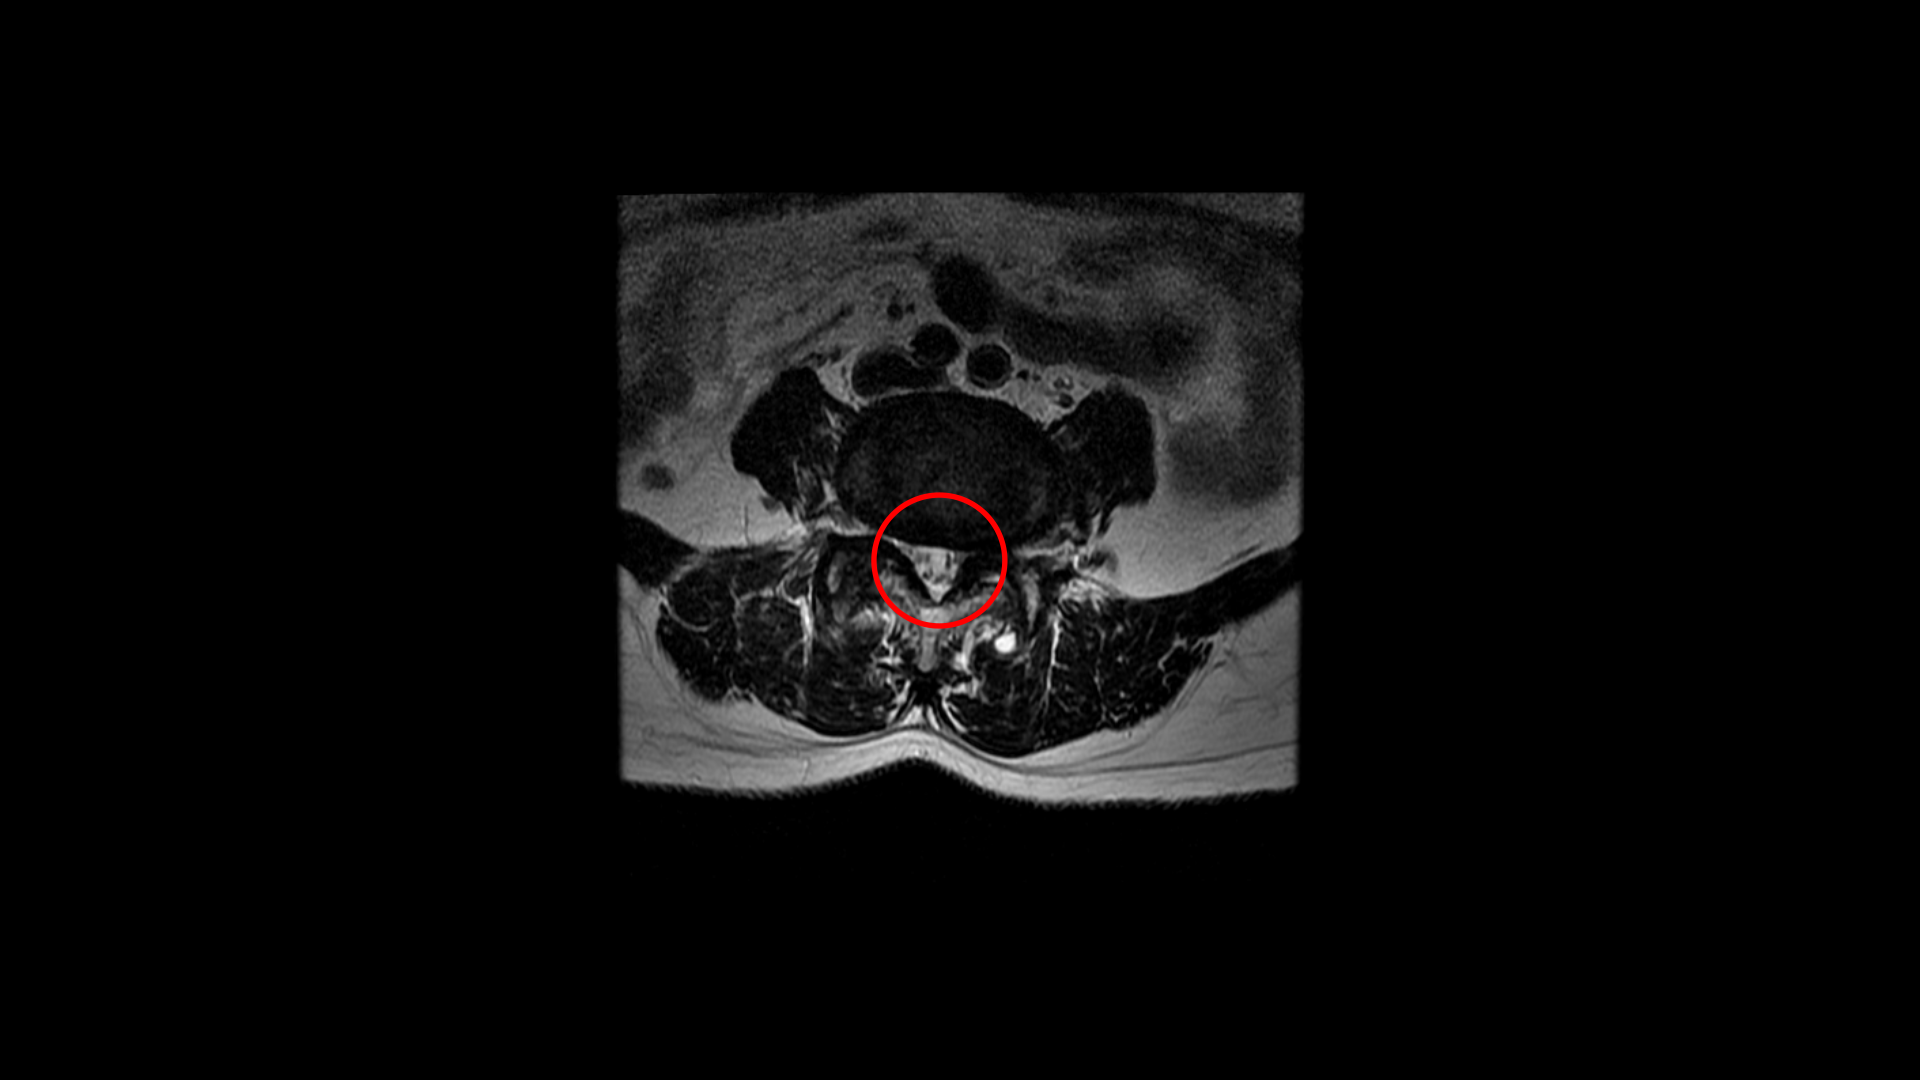

우선 이 환자분의 MRI를 함께 보겠습니다. 이 환자분의 척추에는 3번 4번과 4번 5번에 각각 1단계의 전방전위증이 있습니다.

3번 4번에는 왼쪽으로 디스크 탈출이 있고

중심성 협착도 있습니다.

그런데 이 환자분의 제일 불편한 증상은 왼쪽이 아니고 오른쪽 엉치와 다리 증상입니다. 이분 오른쪽 신경 구멍들을 보면 전부 다 넓게 잘 열려 있습니다.

엉치와 다리 방사통을 일으킬만한 특별한 신경 눌림이 보이지 않는 것입니다. 그럼에도 불구하고 여러 마디의 전방전위증과 척추관 협착 그리고 디스크 탈출이 있으니까 그것을 원인으로 보고 신경 주사도 맞고 시술도 받으셨습니다. 그러나 별 효과는 없었습니다. 그리고 대학병원에서도 결국은 수술밖에 방법이 없다고 수술을 권유하였습니다.